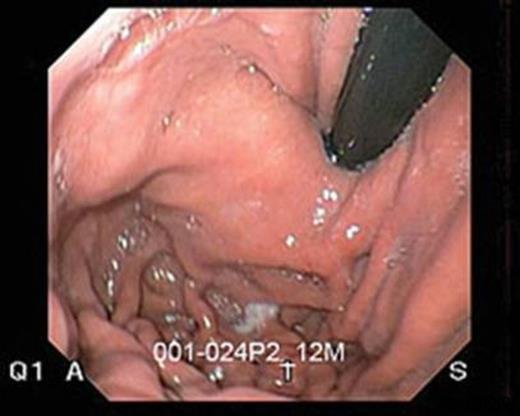

The patient elected to undergo a transoral incision-less fundaplication, in which a 4 cm gastro-esophageal valve was created after the endoscopic application of 14 polypropylene transmural fasteners through the gastric fundus and the distal esophagus (1-3 cm above the Z-line). The procedure also produced a 270 degree endoluminal wrap of the fundus around the intra-abdominal esophagus. (Fig 2) The total operative time was 75 minutes. There were no major intra-operative complications, minimal intra-operative blood loss and the patient was discharged home the morning after surgery.